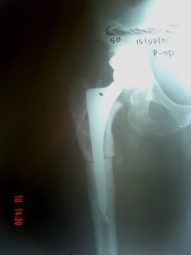

Prótesis Total de Cadera

Envíado por Dr. Ricardo Antonio Gómez G.